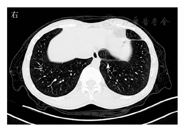

患者男,30岁。因"反复胸闷5个月余"于2020年4月3日收入徐州医科大学附属宿迁医院呼吸科。患者5个多月前无明显诱因出现咳嗽、咳痰,咳少许白黏痰,伴胸闷不适、呼吸不畅,无胸痛、咯血,无发热、盗汗,无心慌、心悸。外院胸部CT检查示:左肺散在条索影,考虑炎症,左侧胸腔积液。胸腔多普勒超声检查示:左侧胸腔见深约70 mm的液性暗区。拟诊断为"左侧结核性胸腔积液",2019年11月17日首次入住徐州医科大学附属宿迁医院呼吸科,血常规检查示白细胞计数为11.32×109/L,中性粒细胞比例为0.245,淋巴细胞比例为0.175,嗜酸性粒细胞比例为0.532,嗜酸性粒细胞计数为6.02×109/L;粪便常规检查未见虫卵和夏科-莱登结晶;生物化学检查未见异常。胸腔积液检查示淡黄、混浊,白细胞计数为7 173×106/L,葡萄糖为0.39 mmol/L,腺苷脱氨酶为96.2 U/L;痰涂片未发现抗酸染色阳性杆菌;支气管镜检查示支气管内未见异常,左下叶背段刷检未见肿瘤细胞,未见抗酸染色阳性杆菌。予利福平(0.45 g/d)、异烟肼(0.3 g/d)、乙胺丁醇(0.75 g/d)、吡嗪酰胺(1.5 g/d)进行诊断性抗结核治疗。多普勒超声检查示胸腔积液吸收。复查胸部CT示左下肺索条影,考虑炎性病变,左侧斜裂胸膜增厚。1个月后门诊复查多普勒超声示左侧胸腔积液较前吸收。2020年2月初患者再次出现胸闷,多普勒超声检查示右侧胸腔积液,外院考虑为"炎性胸腔积液",停止抗结核治疗,加强抗感染治疗,2月27日多普勒超声和胸部CT检查示右侧胸腔积液量较前增多。4月3日再次因"胸腔积液"入住徐州医科大学附属宿迁医院呼吸科。病程中患者偶有发热,体温最高达37.6 ℃,无胸痛、腹痛、头痛、抽搐。既往有阑尾炎手术史5年。入院后体格检查:体温为36.8 ℃,心率为99次/min,呼吸为18次/min,血压为143/93 mmHg(1 mmHg=0.133 kPa)。患者发育正常,营养稍差,神志清楚,精神一般,无气喘貌,步入病房。右季肋部胸壁可触及2枚皮下结节,最大直径约为1 cm。两肺呼吸音低,未闻及干湿啰音。4月4日尿常规检查示潜血(±),红细胞数为15个/μL。粪便常规未检出虫卵和夏科-莱登结晶。生物化学检查示:球蛋白为35.6 g/L,尿酸为917.5 μmol/L,血糖、血脂、电解质正常,心肌酶谱正常。凝血功能:纤维蛋白原为1.63 g/L,D-二聚体正常。胸部CT检查示右侧液气胸,右肺少许斑片索条影,见图1。血常规:白细胞计数为7.56×109/L,中性粒细胞比例为0.170,淋巴细胞比例为0.168,嗜酸性粒细胞比例为0.598,中性粒细胞计数为1.29×109/L,淋巴细胞计数为1.27×109/L,嗜酸性粒细胞计数为4.52×109/L,红细胞计数为5.18×1012/L,血红蛋白为149 g/L,血小板计数为154×109/L。肿瘤标志物检查示:AFP、癌胚抗原、糖类抗原19-9、神经元特异性烯醇化酶(neuron specific enolase,NSE)、鳞状细胞癌相关抗原(squamous cell carcinoma antigen,SCCA)、细胞角蛋白19片段(cytokeratin-19-fragment,CYFRA21-1)均在正常范围内。4月5日行胸腔闭式引流术,胸腔积液常规检查示:血性、浑浊,李凡他试验阳性,无凝块,白细胞计数为8 260×106/L,多叶核细胞百分比为65.2%,单叶核细胞百分比为34.8%。生物化学检查示:总蛋白为80.3 g/L,白蛋白为33.2 g/L,葡萄糖为0.27 mmol/L,腺苷脱氨酶为80.5 U/L。结合患者4月3日入院后体格检查见胸部皮下包块,嗜酸性粒细胞增多,CT检查见"隧道征",考虑肺吸虫感染可能,详细追问病史,患者平素喜食蛇胆、螃蟹、小龙虾。进一步采集血标本和痰标本送至南京金域医学检验所有限公司,查血标本显示肺吸虫抗体(+),痰标本未找见肺吸虫虫卵,诊断为肺吸虫病。4月14日转入徐州医科大学附属宿迁医院感染科,进一步查头颅MRI示脑实质未见异常信号灶,脑室系统形态、大小未见异常。胸腔积液常规检查示:黄色、浑浊,李凡他试验阳性,无凝块,白细胞计数为28 549×106/L,多叶核细胞百分比为62.4%,单叶核细胞百分比为37.6%。胸腔积液生物化学检查示:总蛋白为74.1 g/L,白蛋白为32.7 g/L,葡萄糖为0.40 mmol/L,腺苷脱氨酶为101 U/L。予吡喹酮500 mg口服(3次/d), 3 d为1个疗程,治疗3个疗程。驱虫治疗1个疗程后胸腔积液消失,3个疗程后复查血常规:白细胞计数为3.42×109/L,嗜酸性粒细胞比例为0.158,嗜酸性粒细胞计数为0.54×109/L,中性粒细胞计数为1.76×109/L,淋巴细胞计数为0.88×109/L,生物化学检查无异常,胸部CT检查示仅留有双侧胸膜肥厚,右肺少许斑片索条状影。

肺吸虫病主要是由成虫定居、幼虫游走和虫卵造成的机械损伤,以及虫体代谢产物造成的机体免疫反应而致病,可累及肝脏、肺、胸腔、眼、脑、皮下组织等多个组织、器官。卫氏并殖吸虫所致的肺吸虫病可引起以肺部病变为主的全身症状,临床表现主要有咳铁锈色或烂桃样血痰、咯血。斯氏狸殖吸虫所致肺吸虫病主要表现为游走性皮下包块和渗出性胸膜炎[5]。根据疾病进展,肺吸虫病可分为急性期和慢性期。急性期为囊蚴摄入至幼虫移行阶段,可出现发热、腹痛、腹泻等。慢性期为肺吸虫侵入肺部形成囊肿、瘢痕并产生虫卵的时期,该阶段主要表现为咳嗽、咯血[9]。根据不同的受累部位,肺吸虫病可分为胸肺型、腹型、脑脊髓型、皮肤型和混合型[10],感染虫体数量越多时,越容易发生肺外型感染[11,12]。本例患者以咳嗽、咳痰、胸闷为主要表现,CT检查表现为胸腔积液和肺部索条状高密度影,同时右侧胸壁可触及2枚皮下结节,故诊断为胸肺型及皮肤型混合感染。

绝大多数肺吸虫病患者可见白细胞计数及嗜酸性粒细胞计数增高,白细胞计数可高达56.6×109/L,嗜酸性粒细胞比例和计数分别可高达0.72和37.356×109/L[13]。此例患者两次入院时嗜酸性粒细胞计数和比例均明显升高。嗜酸性粒细胞计数和比例增高还可见于过敏性疾病、血液系统疾病和其他寄生虫感染等疾病,应结合流行病学史及其他检查指标综合考虑[14],以避免误诊。嗜酸性粒细胞计数和比例在驱虫治疗后可恢复正常,可作为诊断依据及疗效评价的简易指标。肺吸虫病患者有浆膜腔积液时,积液检查可见嗜酸性粒细胞、乳酸脱氢酶、腺苷脱氨酶、IL-5等增高,葡萄糖降低。当有上述情况时,结合流行病学史应考虑肺吸虫病[15,16]。肺内影像学表现分为3期:组织破坏期、组织反应期和纤维瘢痕期。由于虫体不断移行,以上3期表现常同时存在,其中"隧道征"较有特异性,对肺吸虫病的CT诊断具有较高的提示意义[17] 。免疫学检查及活组织检查对肺吸虫病的诊断具有重要意义。抗原及抗体检测均具有较高的阳性率,后者的血清抗体检测阳性率较前者更高,可作为肺吸虫病的诊断依据。活组织检查找到虫体或虫卵是诊断肺吸虫病的金标准,当病理检查见嗜酸性粒细胞浸润、嗜酸性肉芽肿时,可考虑肺吸虫感染。肺吸虫幼虫在组织中移行可导致组织损伤,活组织检查时可见隧道样结构,能进一步支持肺吸虫病的诊断。